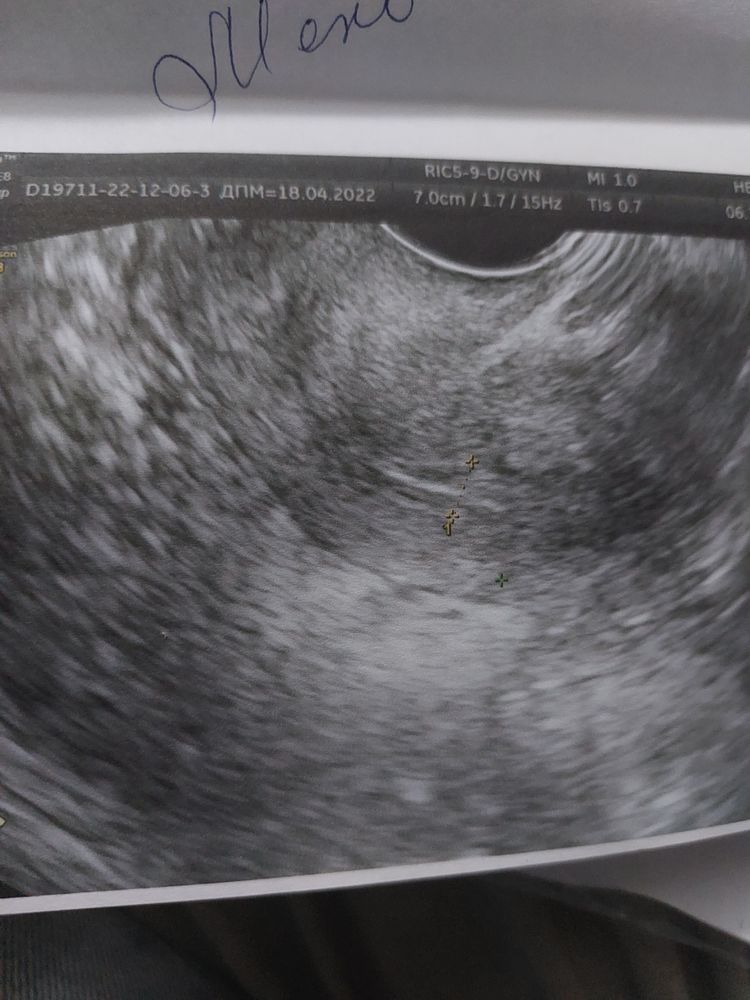

Стимуляция яичников и рост эндометрия: ожидания и надежды

Ну что-ж. Первая стимуляция, и яичники молчат, фоликулы по 4мм. Зато эндометрий подрос 6мм(было4). Ждём 22.12 типа должен начаться цикл, и с 26.12 снова Клостилбегит по 50мг 5 дней. Посмотрим что с этого получиться🙏❤️+ витамины пью: Йодофол и во вторую фазу Енат400